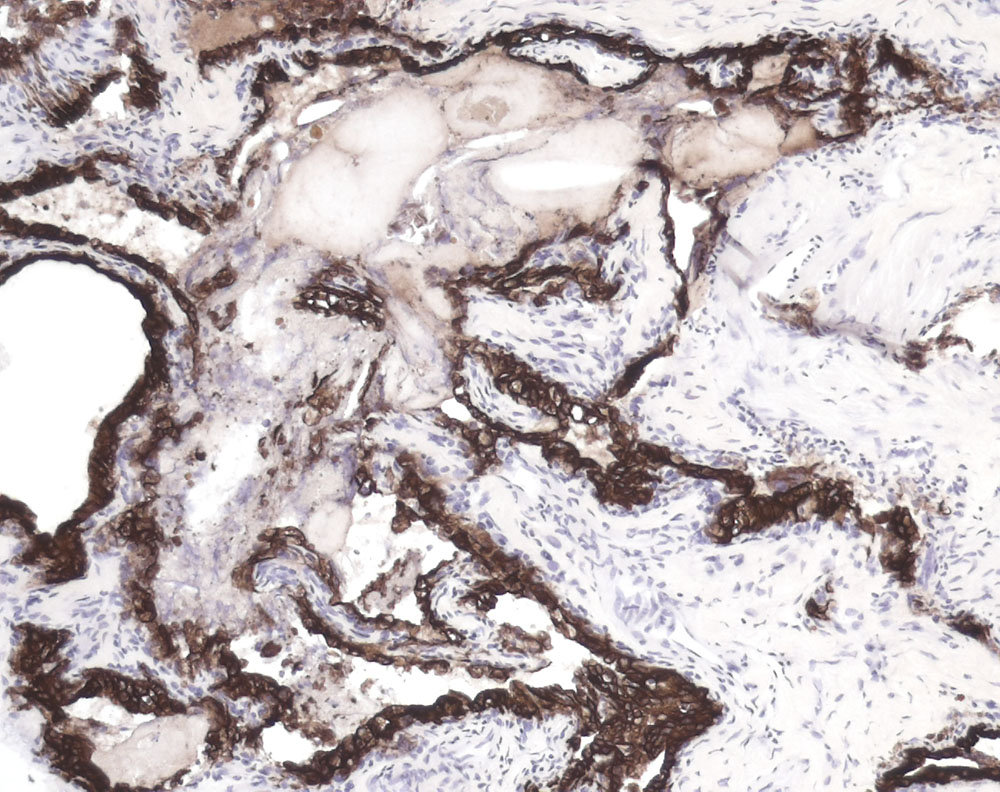

Der Tumor bildet Papillen und glanduläre Strukturen. Die tubuloglandulären Strukturen werden ausgekleidet von einem einreihigen niedrigen kubischen Epithel, welches positiv ist für CAM 5.2 (CK8/18).

Resultat der immunhistochemischen Untersuchungen: Zytokeratin CAM5-2: Alle Tumorzellen stark positiv. S100 und GFAP: Ein Teil der Tumorzellen schwach positiv. Thyreoglobulin: negativ.

Histologie

Immunhistochemie

CK8/18 (CAM 5.2)

100